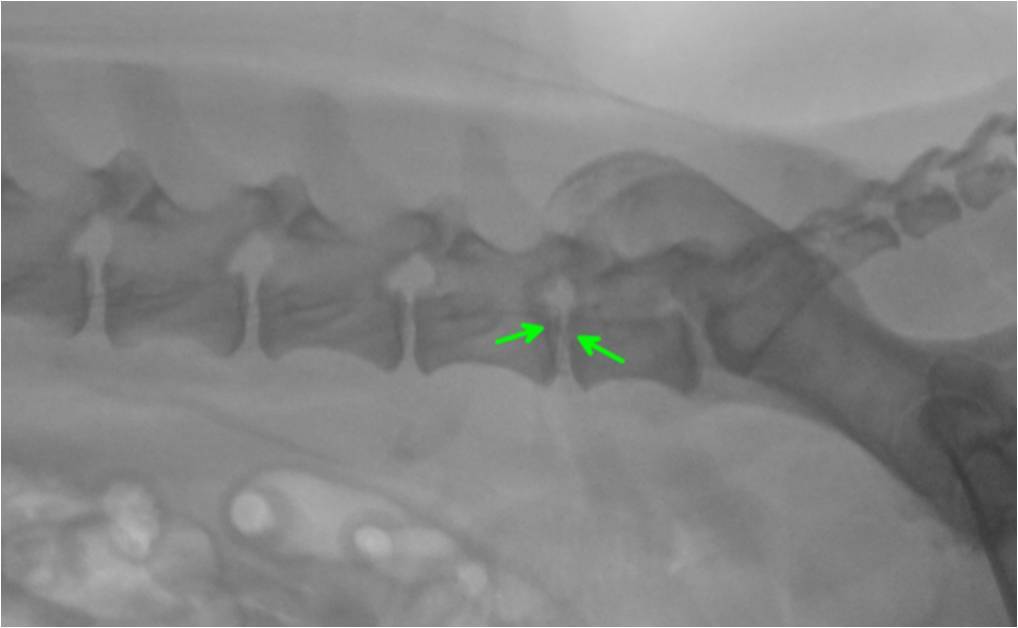

Zurück zu „Quickstep“. Gemeinsam mit den Besitzern des Hundes wurde die Entscheidung zu einem chirurgischen Vorgehen im unmittelbaren Anschluss an die computertomographische Untersuchung getroffen. Es wurde eine sogenannte Hemilaminektomie durchgeführt (Bild 4). Bei dieser Operationstechnik wird der knöcherne Wirbelkanal halbseitig auf Höhe einer Bandscheibe eröffnet, indem mittels einer Fräse und weiteren speziellen Instrumenten die Anteile des Wirbelbogens und der Zwischenwirbelgelenke entfernt werden. Dadurch bekommt man Zugang zum Rückenmark und dem vorgefallenen Bandscheibenmaterial. Dieses konnte bei „Quickstep“ dadurch entfernt werden und eine Dekompression des Nervengewebes erreicht werden. Ob und wie weit sich dieses erholt mussten nun die nächsten Wochen zeigen. Bei der Entlassung aus der Klinik konnte er selbstständig, auch wenn noch etwas unsicher in der Hinterhand, gehen. Es wurde eine strikte Ruhighaltung über acht Wochen verordnet sowie in den ersten sechs Tagen ein Antibiotikum und für zehn Tage ein Schmerzmittel.